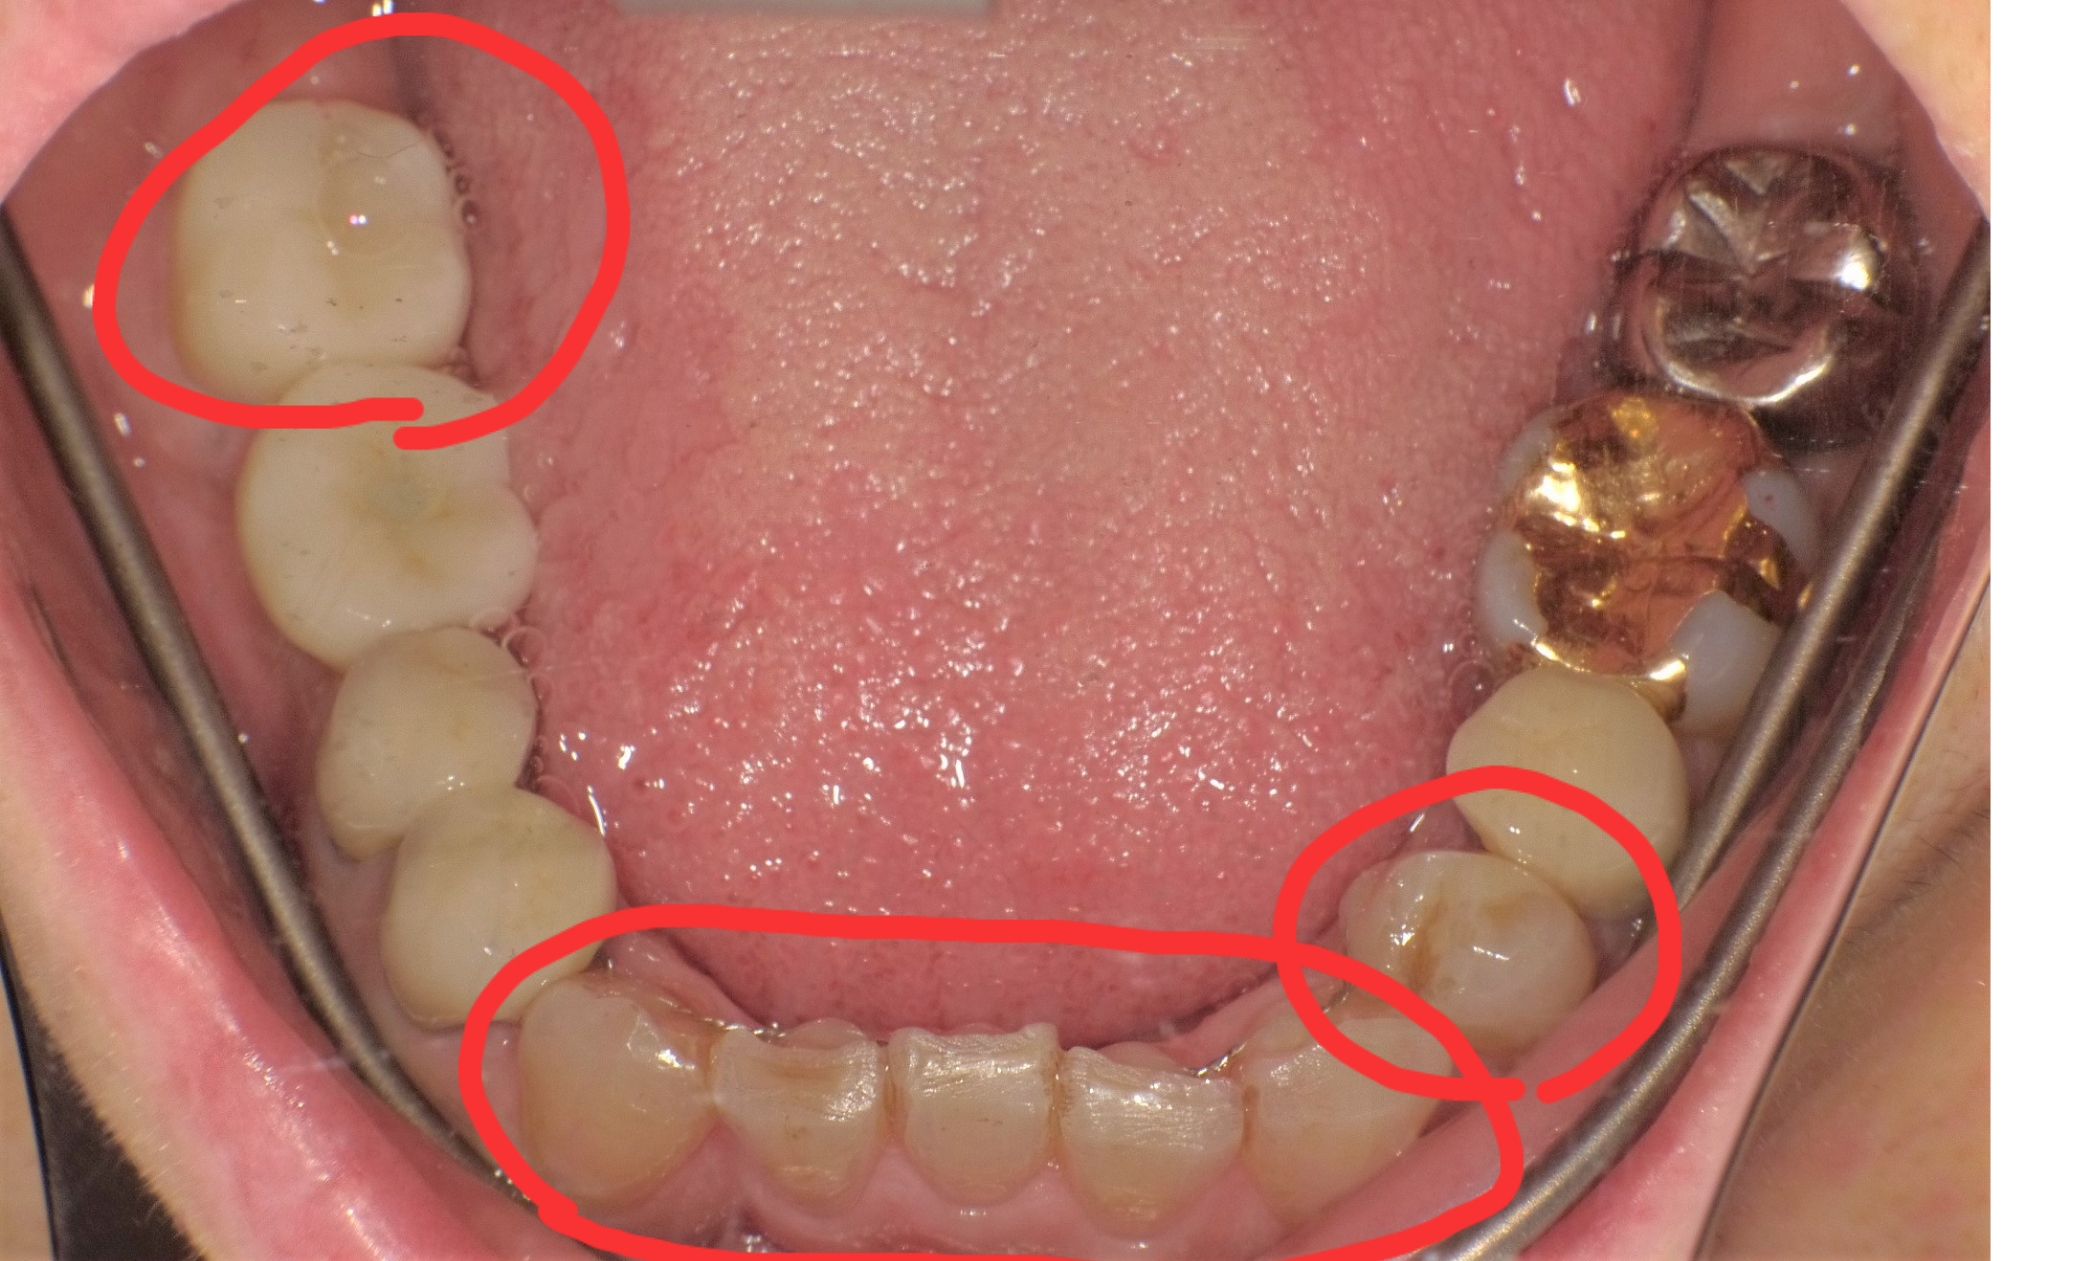

下の写真は治療前と治療後の写真です。

前歯の歯並びと銀歯を白いセラミックに治しました。歯並びは部分矯正で綺麗に並び手前の歯の銀歯は保険の白い詰め物をして奥の歯はセラミックが入りました(*^_^*)部分矯正は3~4ヶ月で下の写真のように綺麗に並んできます!